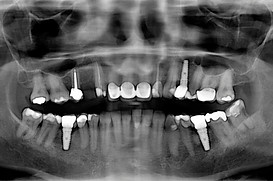

Zygomatic implants are a game-changer for patients with severe bone loss, but mastering this advanced technique requires specialized training. With so many courses available globally, choosing the right one can be challenging.